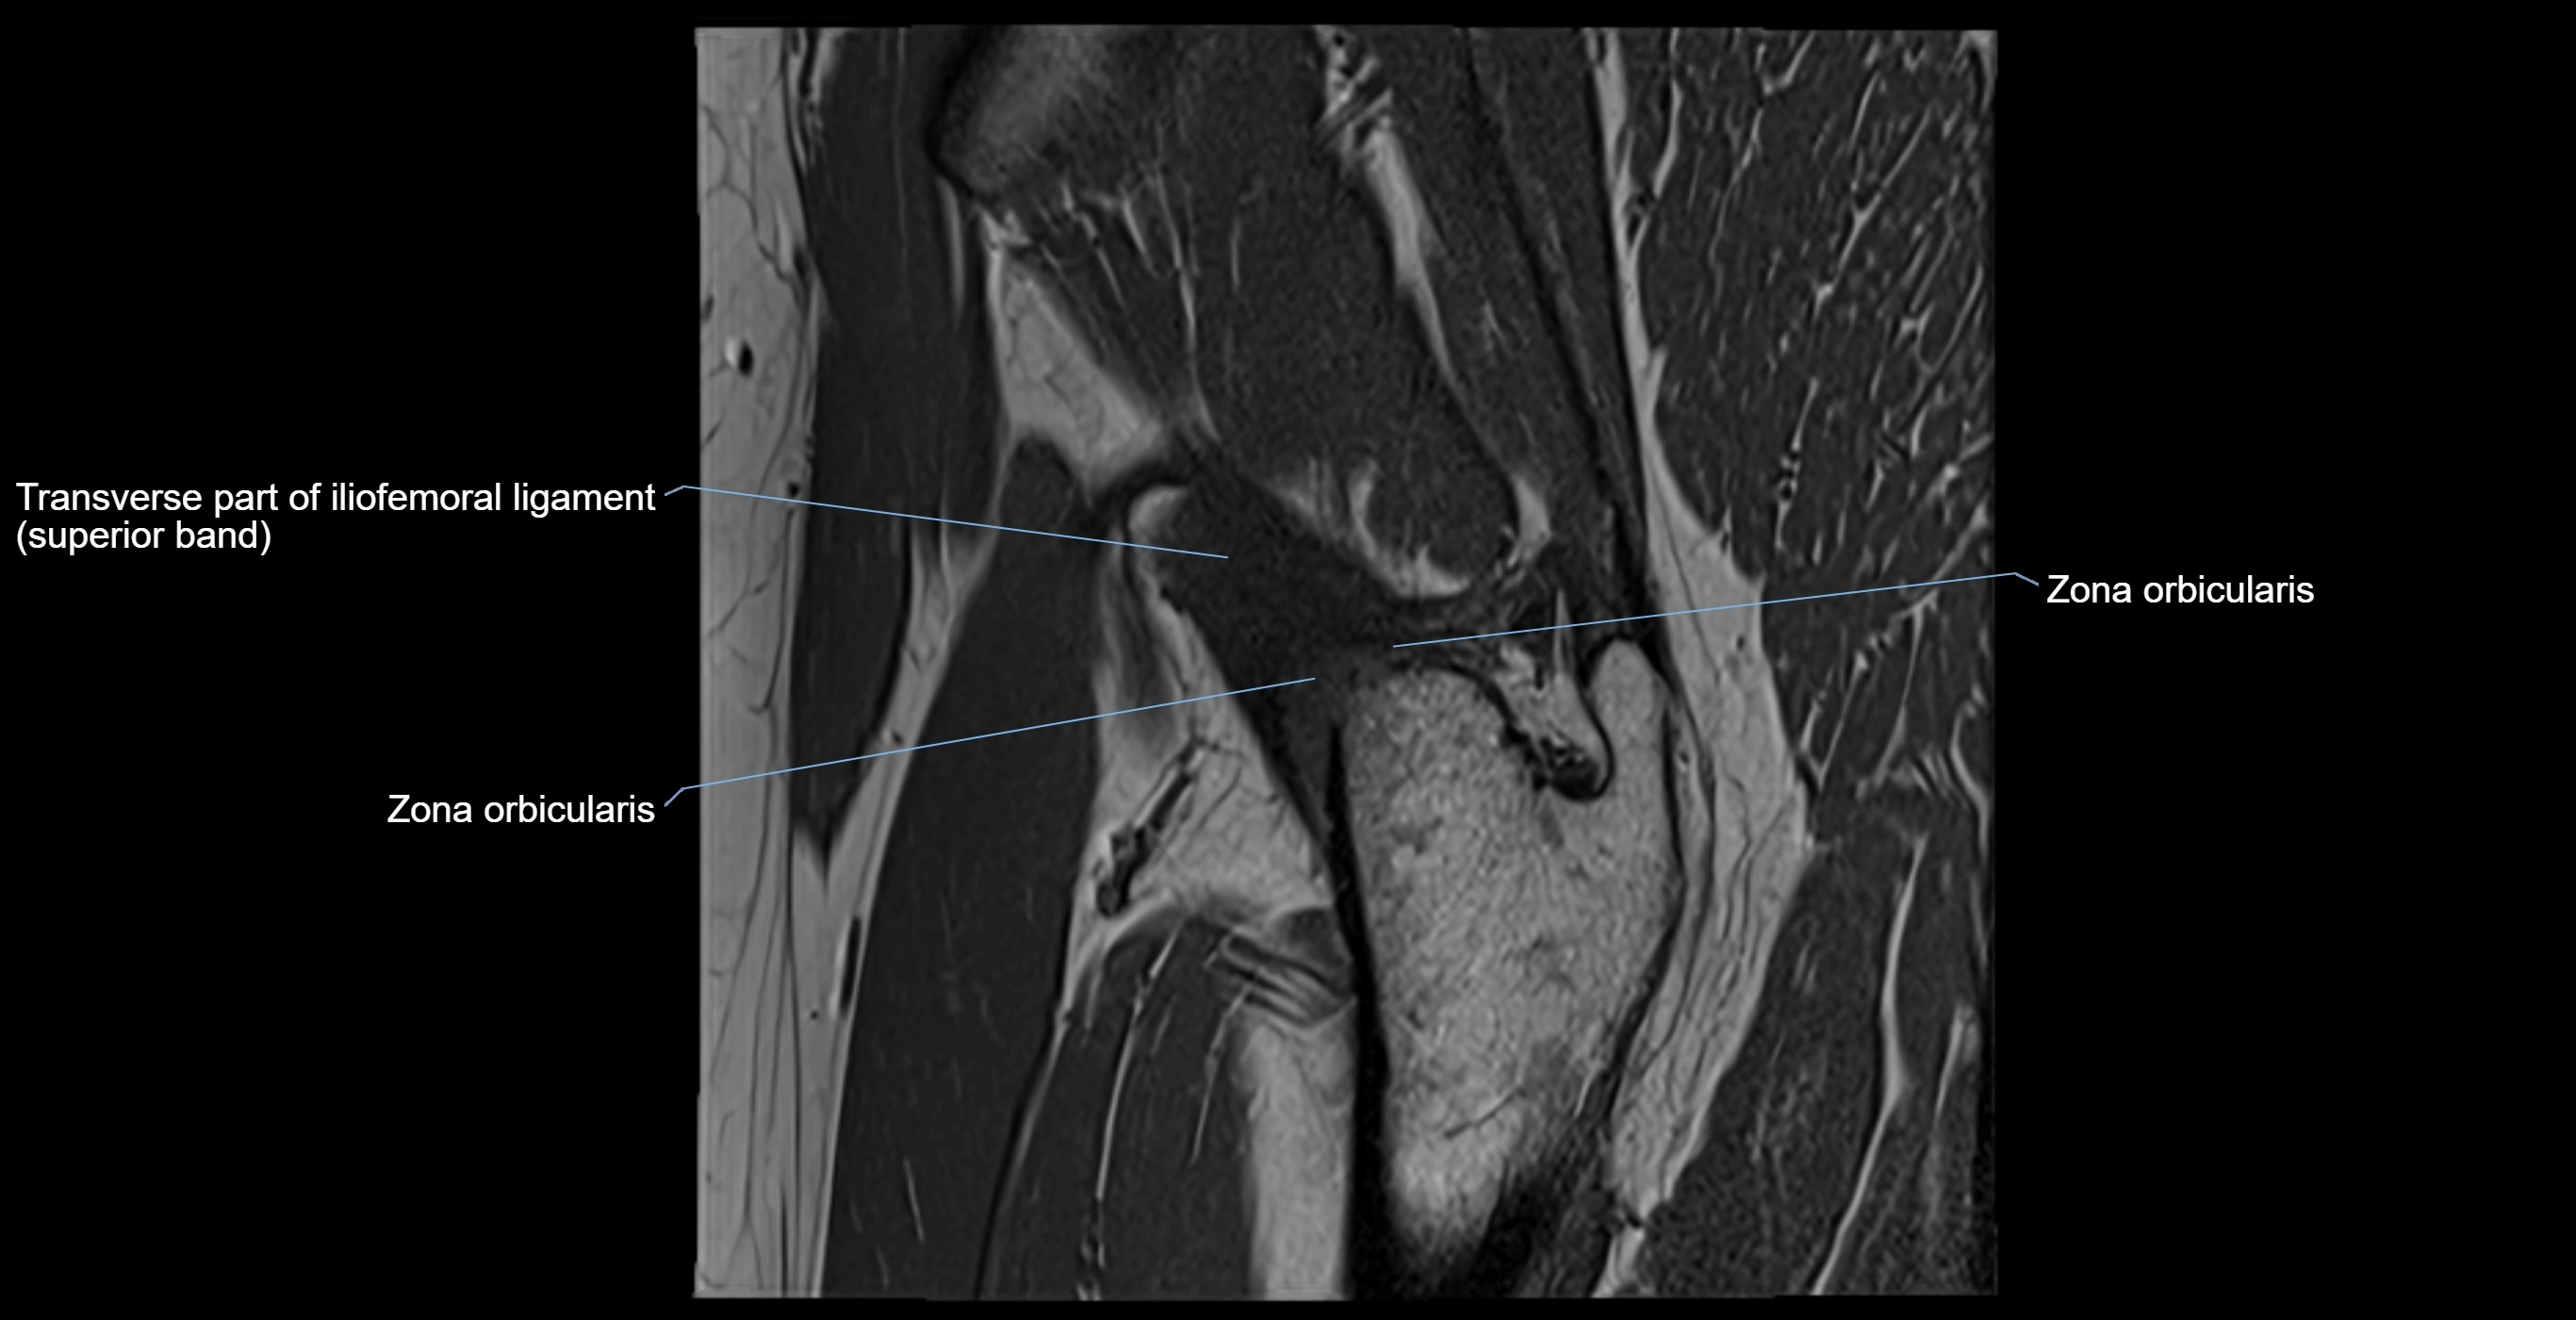

MRI Appearance

T1-weighted images:

• Labrum: low signal intensity (dark)

• Surrounded by intermediate signal joint fluid (bright on arthrogram)

• Tears: linear or focal areas of intermediate-to-high signal interrupting labral continuity

T2-weighted images:

• Joint fluid: bright, making labral tears visible as fluid extending into or around labrum

• Degeneration: may show areas of increased signal within labrum

MRI image

image